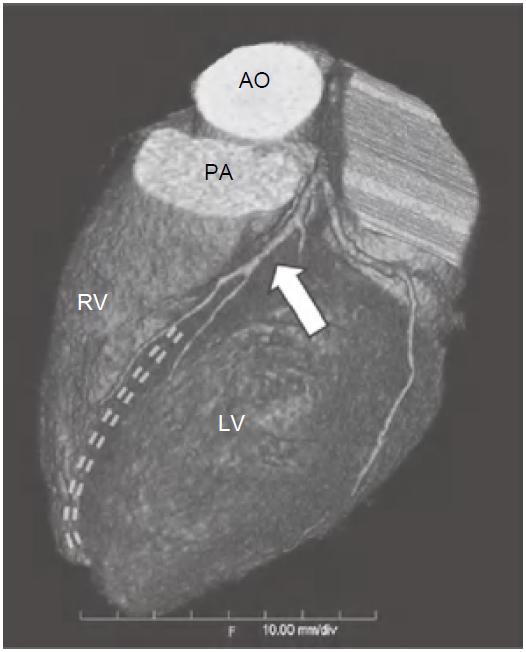

冠状动脉左主干(LMS)通常起源于左冠窦,位置低于RCA开口平面。通常在左心耳及肺动脉主干之间走行约1~2cm后分为LAD及左旋支(LCX),LAD在前室间沟内向下延伸至心尖(图13-1),LCX在左房室间沟(LAVG)内向后走行(图13-2)。

图13-1 左前降支(箭)起自左主干分叉处,并在前室间沟(虚线)内走行,为前壁、心尖部及大部分室间隔供血

AO.主动脉;PA.肺动脉;RV.右心室;LV.左心室